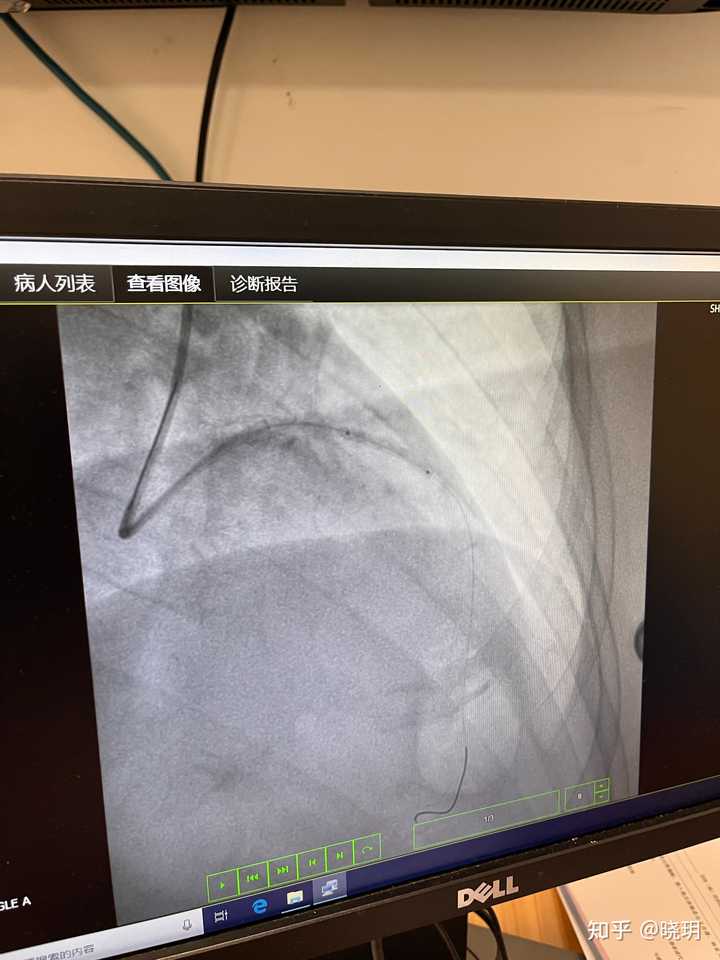

我应该是第一次搭120救护车,有点冷,摇摇晃晃的,一路到市医院。到了以后,县医院来之前已经联系好医生和科室了,随即给我换了病床就直接推进手术室了。

大概三四个医生,对我身体一顿捣鼓,我听到医生在旁边感叹:血栓真多!血栓太多了!怎么血栓会这么多!从我右手主动脉插入探针,打造影。确定了我是心脏右边有根血管堵塞,而且,堵塞的前面一小节异常肿大。确定了情况,就开始清理血栓。我可以清晰的感觉到有血栓从我的右胳膊从肩头被什么东西往手上拉,直到从右手主动脉拉出来。整个过程异常难受,而且疼!但是得控制自己不能动,也不能翻身,尤其是右手动脉切开处,疼,但是得忍着不能动。医生说:千万不能动,现在是要命的时候。最终从我堵塞部位附近拉出去20多条三四厘米长的粗粗细细的血栓,医生也惊叹:血栓太多了,太粗了!但是医生也说不出为什么血栓这么多。因为我平常不抽烟,不喝酒,没有高血压,没有高血脂,医生本来还在猜测我平常喝饮料多,事实上,我很少喝奶茶,饮料,我平常都喝水。油炸基本不吃。医生也纳闷,我的生活习惯都不是我会得心梗的条件。只有一个,经常熬夜。所以,最终把一切都归结到了“熬夜”上了。再加上我这段时间减肥,每天只吃一顿,瘦了这么多,严重影响了身体本来的平衡,导致营养不良,贫血,低血压,低血糖。

在普通病房又待了四天,医生说我体内血栓已经溶的差不多了,要再做一次造影针,确定是不是需要做支架。做支架这个事很重要,如果做了支架,就需要每天吃药,以后也不能做剧烈运动,后遗症比较麻烦,所以我们起先商量的就是能不做支架就不做支架。医生说我的各项指标恢复的还不错,大概率不用做支架,但需要做造影针确定下。那天下午,去做造影针,排队的时候心里还是比较忐忑的,给我做手术的医生还是上次的医生,消毒后,给我做的时候,跟我说“有点疼,忍着点”,我立马就感受到右手疼的抖了一下,我立马克制自己不能乱动,医生是从上次进入过的动脉血管处,撕开血管,放进去针,到之前堵塞的位置,注入造影。大概十分钟,结束,医生拍了下我“放心,恢复的不错,不用做支架”,我松了口气,连“谢谢”都忘说了。并且,之前堵塞位置血管肿大的问题,现在也恢复的快正常了。因为是堵塞后血液涨起来,撑大的。可想而知,如果晚一些,血管会被撑的更大,甚至撑爆。那就更麻烦了。